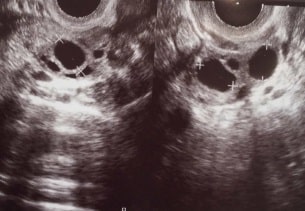

卵巣過剰刺激症候群とは

卵巣過剰刺激症候群 (OHSS)は、不妊治療で排卵誘発剤を使うことで卵巣が腫れで、お腹に水が溜まる状態です。